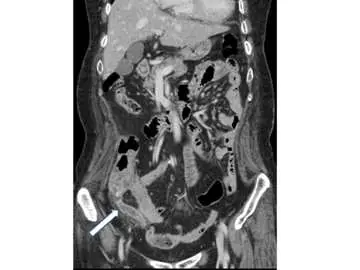

病人主訴右下腹逐漸悶痛、腹脹、反胃一整天。腹部電腦斷層檢查呈現如附圖。箭號所指之異常最符合下列那一項初診斷?

本題提供一張腹部電腦斷層**冠狀面(coronal plane)**重建影像:

- 影像顯示腹腔與骨盆腔的冠狀切面,右側腸道結構清晰可見

- 箭號指向右下腹(右骼窩區域),指向一個管狀、盲端、壁增厚的結構,代表發炎腫脹的闌尾(appendix)

- 該結構直徑明顯擴大(視覺上超過正常 6 mm 閾值),管壁增厚並有強化(wall enhancement)

- 箭號所指區域周圍可見脂肪絞窄(periappendiceal fat stranding)——闌尾周圍脂肪密度增高、模糊,代表局部發炎反應向周圍蔓延

- 整體表現:盲端擴張管狀結構 + 壁增厚 + 周圍脂肪絞窄,高度符合急性闌尾炎的 CT 標準診斷特徵

- 未見明顯游離氣體,目前無穿孔的影像證據